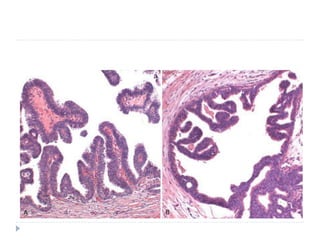

Carcinoma in situ. A low-power view shows that the epithelium is entirely

replaced by atypical dysplastic cells. There is no orderly differentiation of

squamous cells. The basement membrane is intact, and there is no tumor

in the subepithelial stroma.

A high-power view shows failure of normal differentiation, marked nuclear

and cellular pleomorphism, and numerous mitotic figures extending

toward the surface.